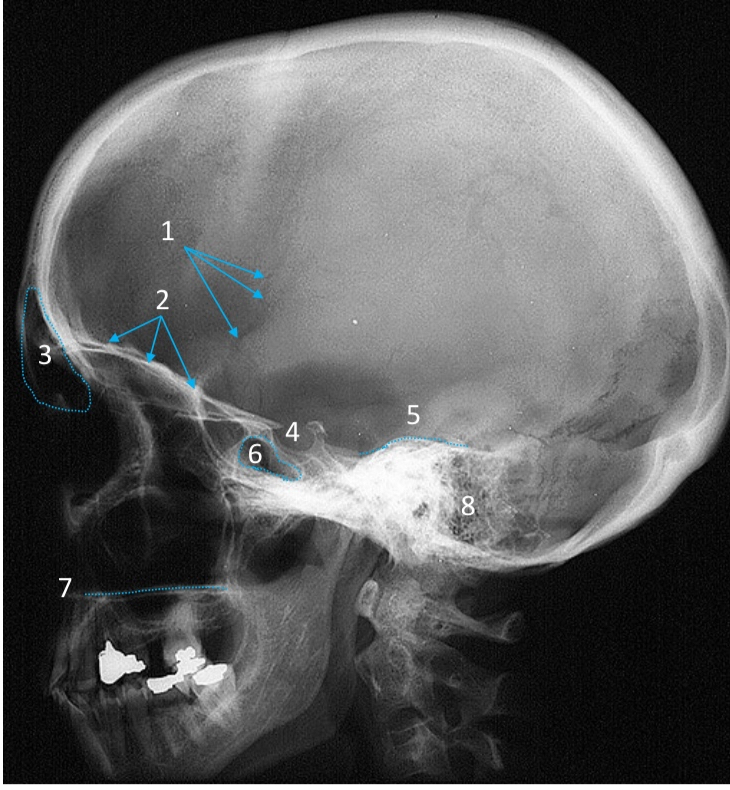

Mandible

ID bone

Maxilla

ID bone

Frontal sinus

ID structure

Pituitary fossa

ID structure

Occipital

ID bone

Lambdoid suture

ID structure

Frontal sinus

ID structure

Orbital margin

Orbit

Maxillary sinus

ID structure

Mandibular condyle

ID structure

Inferior nasal concha

ID structure

Hard palate

ID strucutre

Gonial angle

ID strucutre

Petrous ridge

ID structure

Groove of middle meningeal a.

ID structure

Roof of orbit

ID structure

Frontal sinus

ID structure

Pituitary fossa

ID structure

Petrous ridge

ID structure

Sphenoid sinus

ID structure

Hard palate

ID structure

Mastoid air cells

ID structure

Zygomatic arch

ID structure

Mandibular condyle

ID structure

External auditory meatus

ID structure

Mastoid air cells

ID structure

Foramen magnum

ID structure

Foramen ovale

ID structure

Foramen spinosum

ID structure